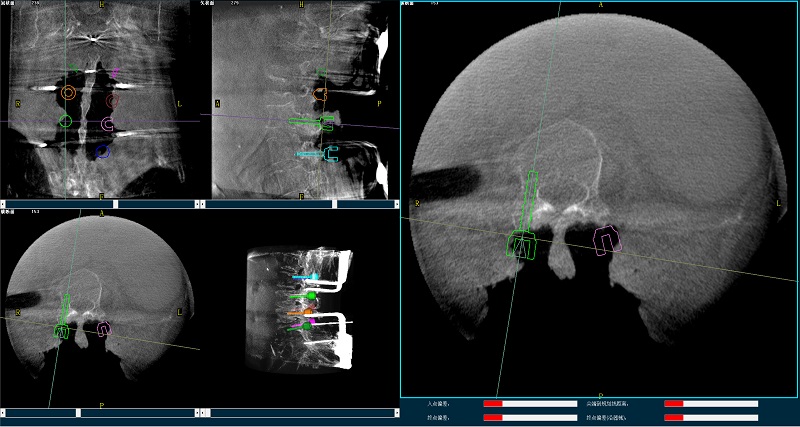

三維圖像

(2)使用普愛醫療平板三維C形臂掃描患者,得到術中三維圖像并傳送至骨科機器人導航系統。骨科機器人導航系統基于高清術中三維圖像進行手術規劃。

手術規劃圖像

(4)在骨科機器人導航系統輔助下,一次性準確植入8枚椎弓根螺釘。